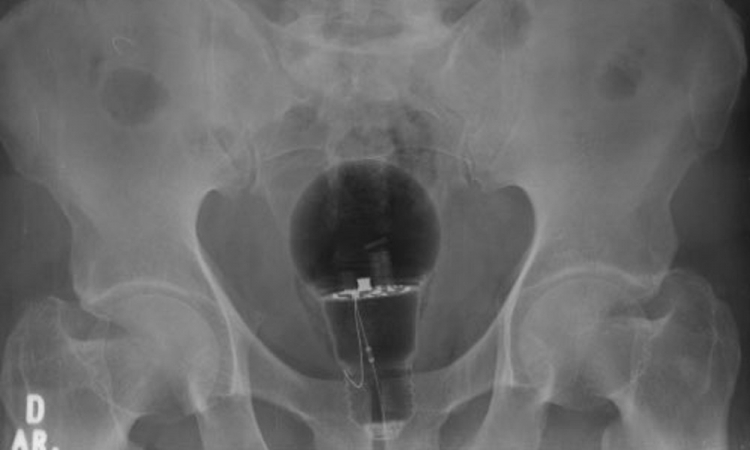

Um caso inusitado aconteceu na Colômbia e foi registrado por um médico nas redes sociais. Um homem, de 53 anos, foi parar no hospital após sentir fortes dores no ânus. Os médicos fizeram exame no paciente e foi constatado que ele estava com uma lâmpada presa no reto. De acordo com veículos locais, o homem estava sofrendo dores há três dias. No entanto, ele só procurou ajuda médica quando a dor ficou intensa.

Depois dos médicos identificarem o problema, o homem comentou que não revelou o que era e nem foi antes para o hospital por medo de que sua esposa descobrisse o que havia acontecido. “O objeto não era palpável ao toque retal. Material de corpo estranho”, escreveu no Twitter o gastroenterologista Julian Pylori, que divulgou uma imagem do raio-x.

A TV Azteca informou que o objeto era de plástico e, assim, não estourou dentro do corpo do homem. A lâmpada foi removida pelos médicos e o paciente passa bem. Nas redes sociais, os internautas ficaram chocados com o episódio. “Isso é recorrente em hospitais. Povo coloca de tudo. Impressionante”, escreveu uma internauta. “O grande questionamento: por quê?”, disse outra. “Um vagalume”, brincou um terceiro.